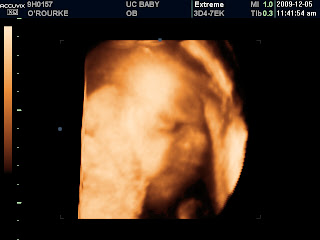

It is absolutely breathtaking that deep within me lies this perfect little being – with big eyes and a precious button nose and expressive lips and cheeks just like Daddy. All those jabs and bumps and jiggles that shake up my belly are caused by little hands with perfect little fingers and little feet containing perfect little toes: